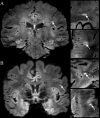

Objective: The diagnosis of multiple sclerosis (MS) presently relies on radiographic assessments of imperfect specificity. Recent data using T2* methodology for the detection of the "central vessel sign" (CVS) in MS lesions suggests this novel MRI technique may distinguish MS from other disorders. Our aim was to determine if evaluation for CVS on 3T FLAIR* MRI differentiates MS from migraine.

Methods: Patients with MS or migraine and a prior brain MRI demonstrating at least two hyperintense lesions ≥3 mm were recruited. Exclusion criteria included any additional comorbidity known to cause brain MRI abnormalities. 3T MRI was performed in each participant with administration of gadopentetate dimeglumine, and FLAIR* images were generated in postprocessing. The total number of discrete ovoid lesions ≥3 mm were counted on FLAIR, per participant, and subsequently evaluated for presence of CVS on FLAIR*. An exploratory method evaluating for CVS in a maximum of 12 lesions per subject was also completed.

Results: Ten participants with MS and 10 with migraine completed the study. The median percentage (quartiles) of lesions in MS participants with CVS was 84 (79, 94) compared to 22 (15, 54) in migraine (P = 0.008). In a subanalysis by brain region, in the subcortical and deep white matter, the median percentage (quartiles) of lesions in MS participants with CVS was 88 (81, 100) compared to 19 (11, 54) in migraine (P = 0.004). This difference was not identified in juxtacortical, periventricular, or infratentorial regions.

Interpretation: Identification of CVS using FLAIR* on 3T MRI helps differentiate MS from migraine, particularly in the subcortical and deep white matter.